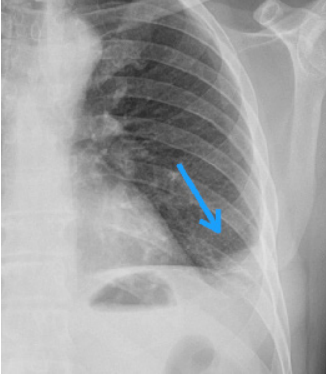

Qual alteração radiológica é possível ser vista neste RX de tórax?

É sinal sugestivo de quê?